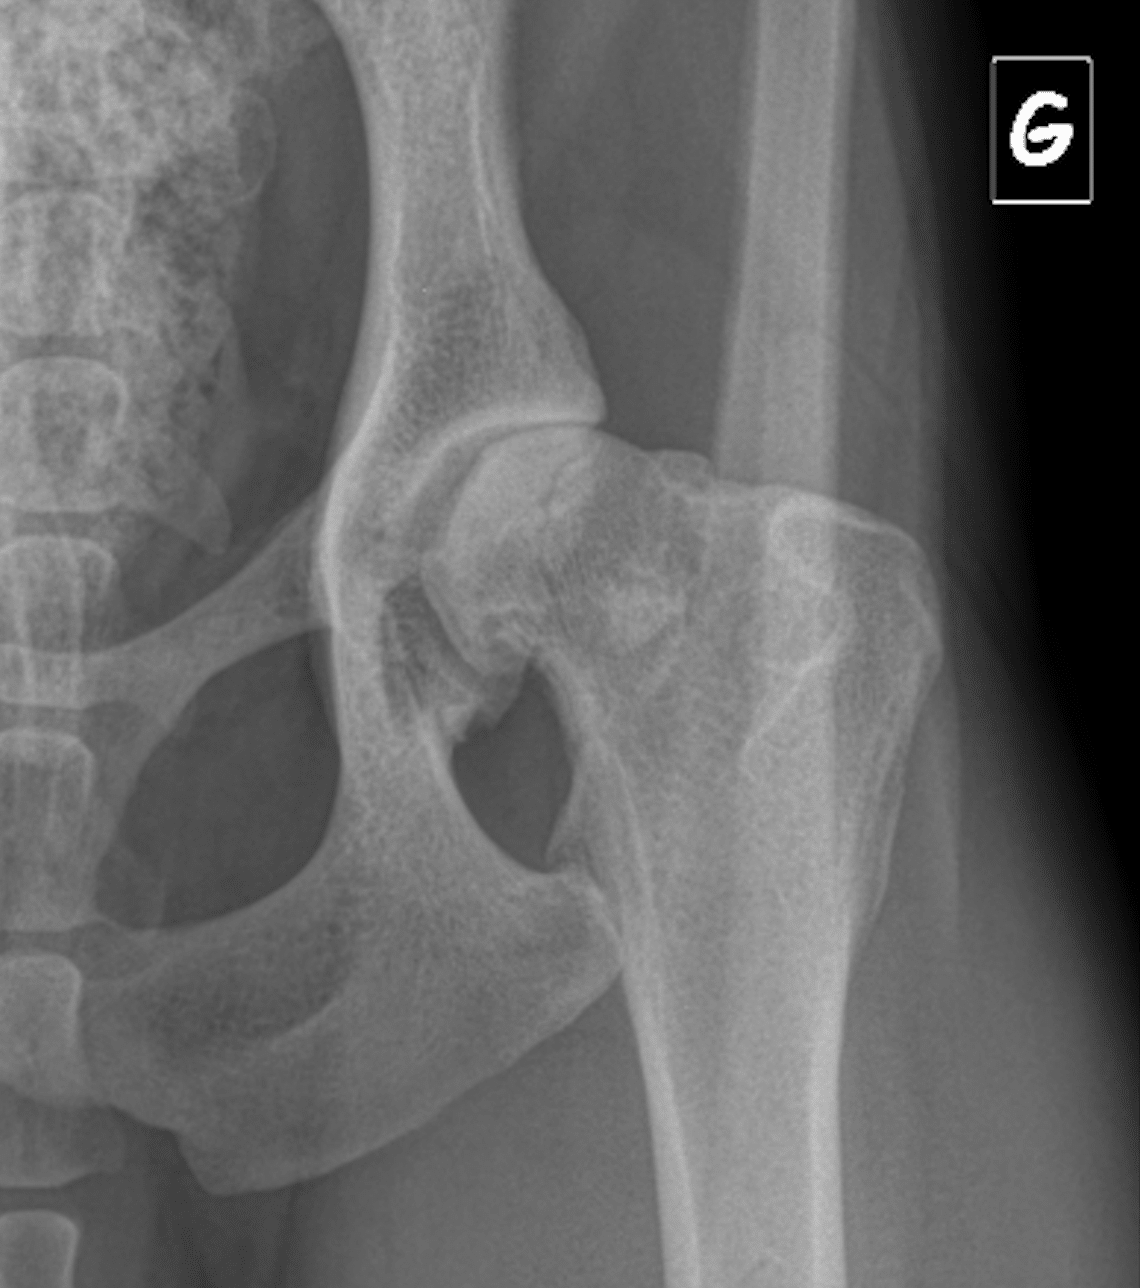

Dysplasie de la hanche chez le chien